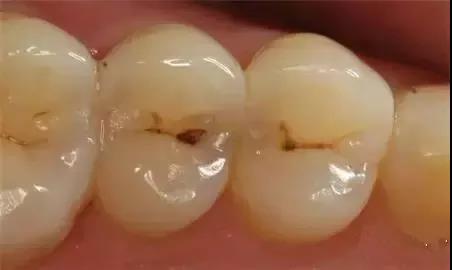

01 浅龋

当我们牙上有小黑点时,您毫不在意地说:“没事的,没感觉。”

牙医说:“龋病是由以细菌为主的多因素导致的牙齿硬组织发生慢性进行性破坏的一种疾病。已经开始浅龋即牙釉质龋,需要做药物治疗或充填治疗。 》》》相关阅读:在廊坊,牙周炎可以治愈吗?